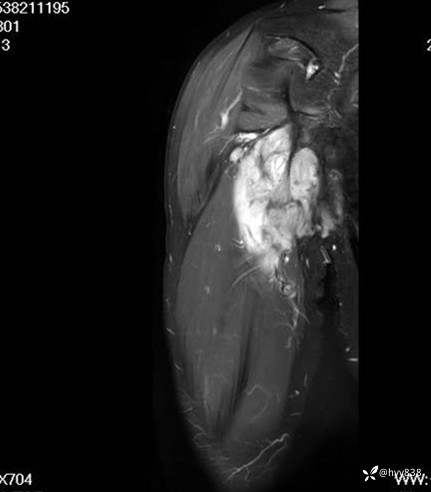

简要病史:4年前无意间发现右上臂包块,约拇指大小,质硬,边界较清,不伴疼痛,近几年来,右上臂包块逐渐增大,约7x7cm大小,皮肤无红肿、破溃。

辅助检查:MRI

MRI AXI T1WI+T2WIfs

SAG T1WI+PDWI fs